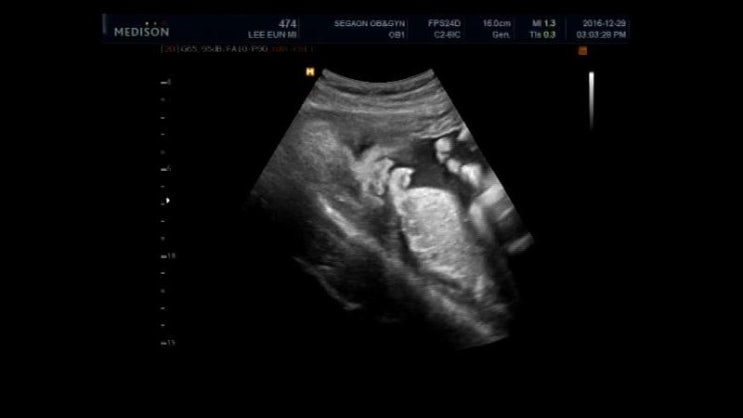

2016년 12월 29일 오복이 36주 6일차

예전엔 임신막달에 일주일에 한번꼴로 검진 받은 기억이 있는데 이번엔 2주에 한번씩 정기검진 받으러 오라...